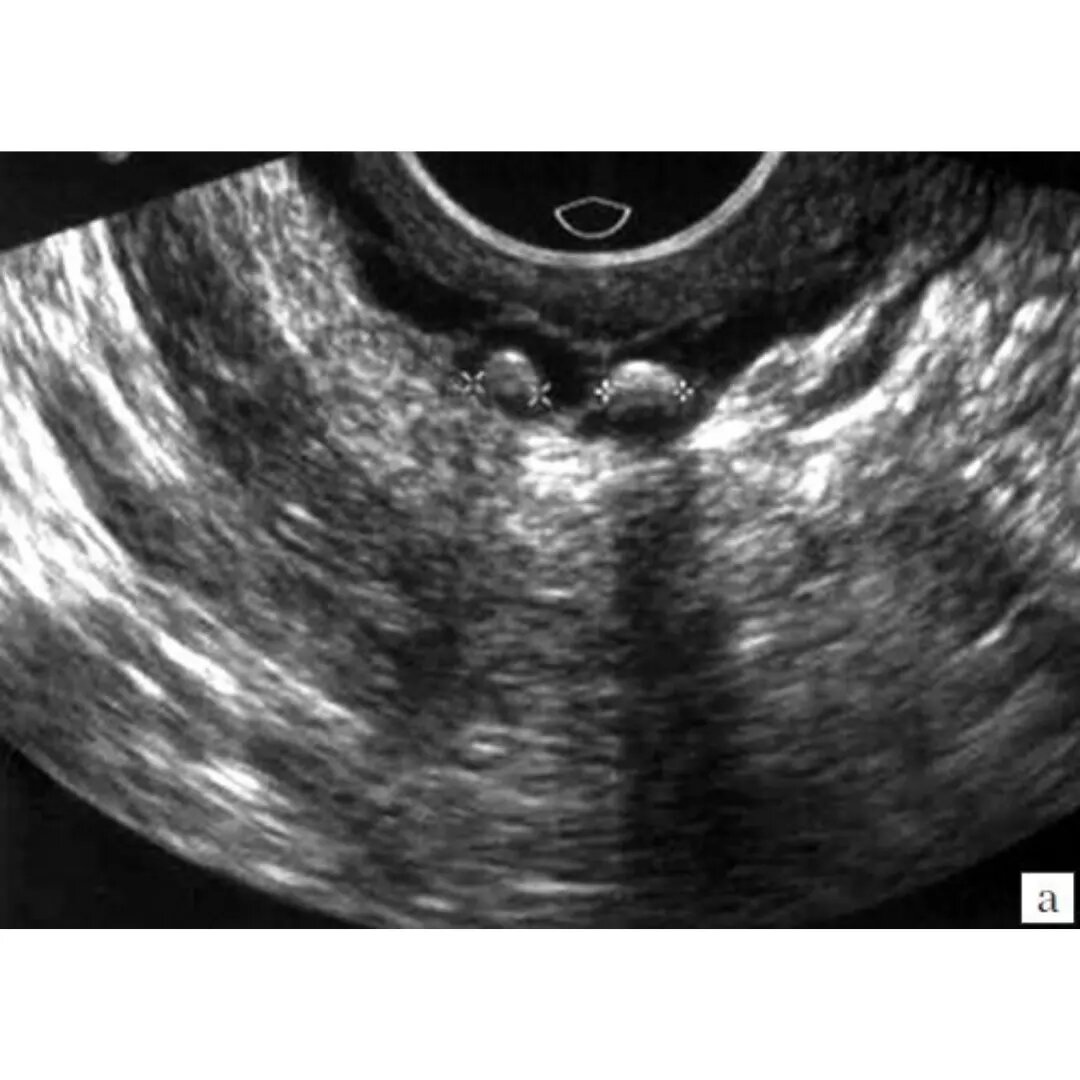

Венозные камни (флеболиты).

Чаще всего венозные камни имеют округлую или овальную форму. Наибольшим диаметром они ориентируются по ходу вены. Небольшие образования (до 4 мм) менее кальцифицированы, чем крупные, что объясняет повышенную рентгеноконтрастность последних.

Поскольку типичных клинических признаков флеболиты не имеют, ведущую роль в их диагностике отводится лучевым методам диагностики венозной системы. При подозрении на внутрисосудистые включения информативны:

🔹 УЗИ